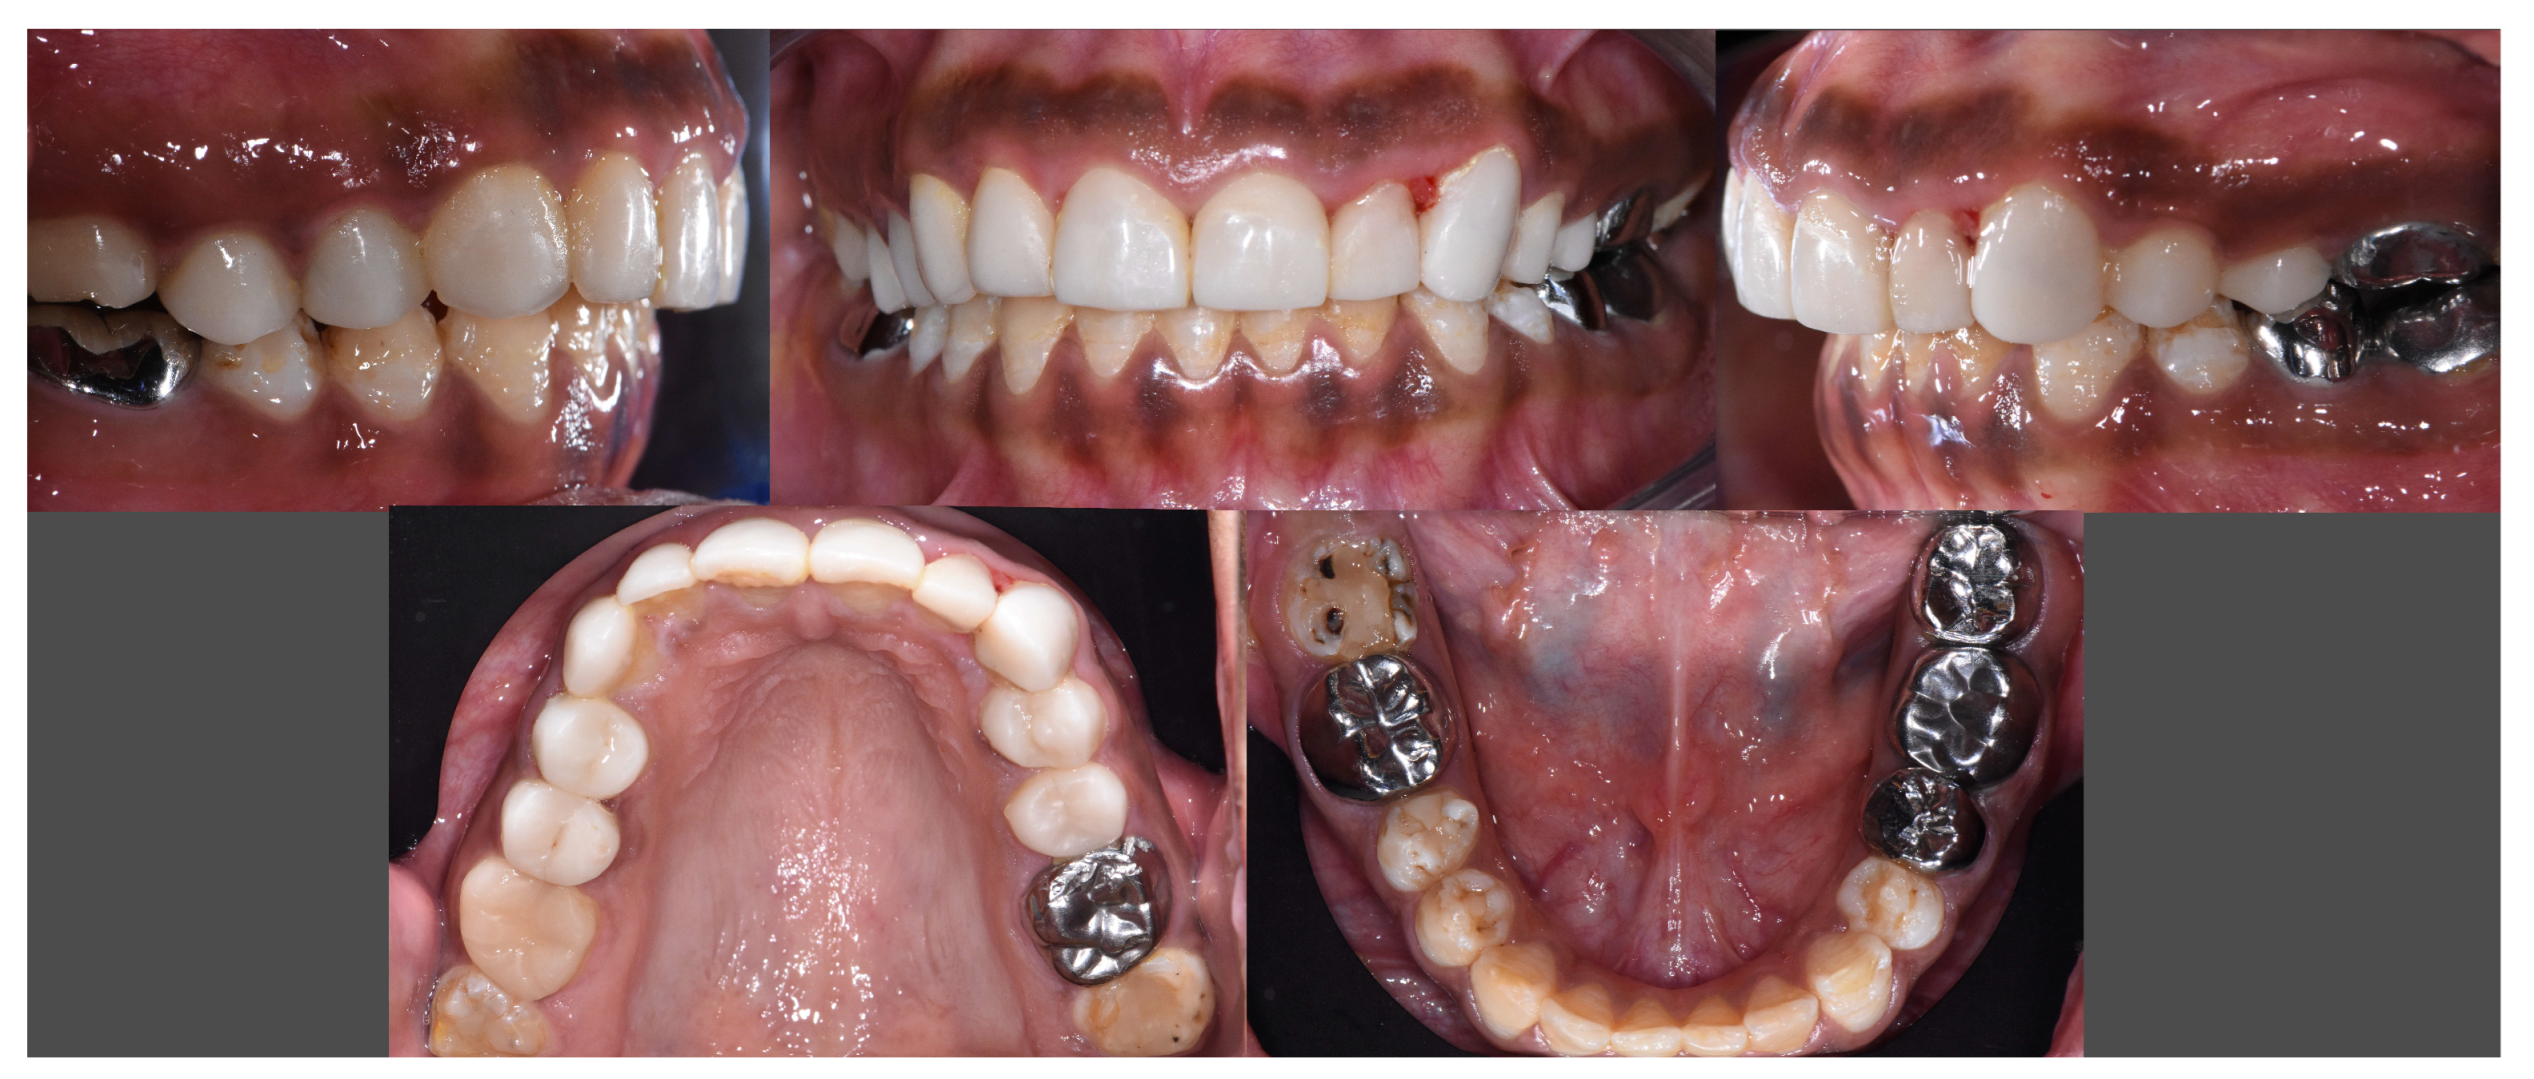

2.11. Follow-Ups

2.11.1. At 15 Days

2.11.2. At 3 Months

2.11.3. At 8 Months

2.11.4. At One and a Half Years

2.11.5. At Three Years